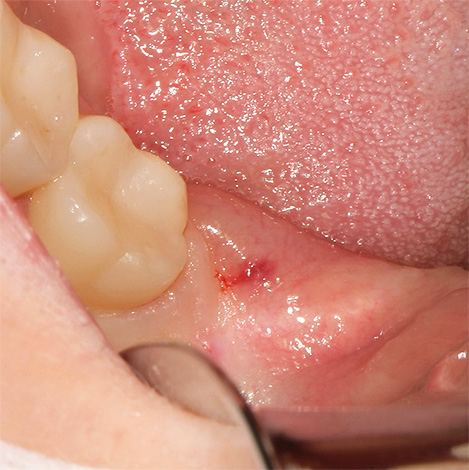

Depois disso, vários médicos preferem fechar a ferida para aproximar suas bordas e evitar os riscos de reinfecção e o desenvolvimento de sangramento espontâneo do orifício (isso não dói, pois o anestésico ainda está agindo). Após a remoção do dente do siso, o dentista faz recomendações para o cuidado do orifício.

Uma visita oportuna a um médico ajudará a evitar complicações graves. Na maioria dos casos, só será necessário limpar o orifício de um coágulo sanguíneo infectado, fragmentos de um dente removido, tecido ósseo, goma traumática, contaminação bacteriana. Além disso, se necessário, pode ser realizado tratamento anti-séptico com a formulação de medicamentos (Alvogyl), suturando as bordas da ferida com a indicação de agentes anti-inflamatórios, antimicrobianos e enxaguamentos anti-sépticos.